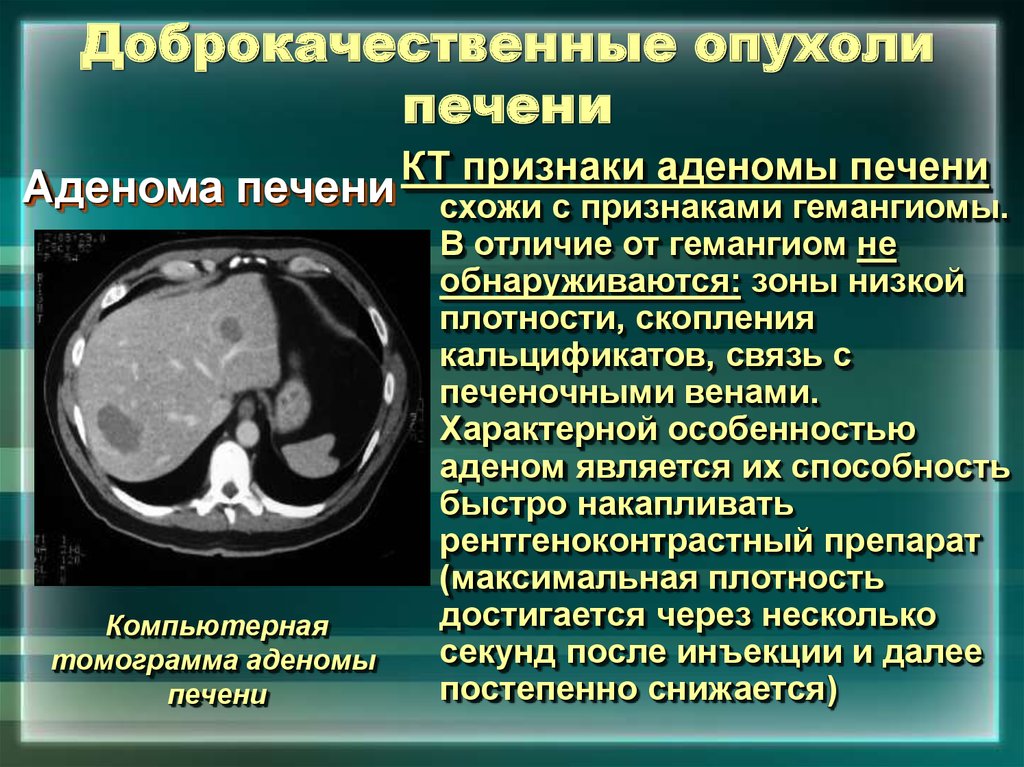

Классификация заболеваний щитовидной железы. Классификация хирургических заболеваний щитовидной железы. Заболевания щитовидной железы классификация этиология. 1. Классификация заболеваний щитовидной железы?. Опухоль печени доброкачественная кт. Первичные злокачественные опухоли печени. Злокачественные новообразования печени кт. Первичные и Метастатические опухоли печени.

Опухоль печени доброкачественная кт. Первичные злокачественные опухоли печени. Злокачественные новообразования печени кт. Первичные и Метастатические опухоли печени. Маммография. Маммограмма молочных желез. Маммография после 40 лет проводится.